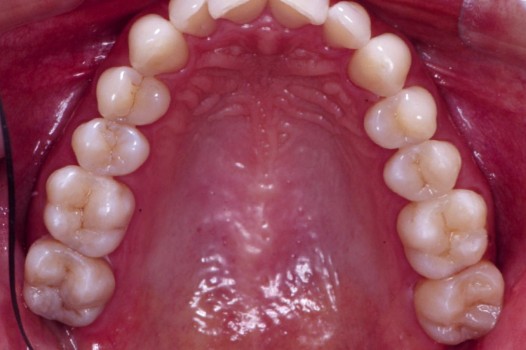

Traditional amalgam (mercury) fillings have been used for over a century, but concerns about health risks, tooth fractures, and long-term decay have led many dentists to adopt modern alternatives. Today, metal-free restorations offer healthier, stronger, and more natural-looking results.

Using advanced resins, ceramics, and state-of-the-art bonding techniques, Dr. Klim can restore teeth with precision, preserving healthy tooth structure while preventing fractures, bacterial invasion, and future toothaches.